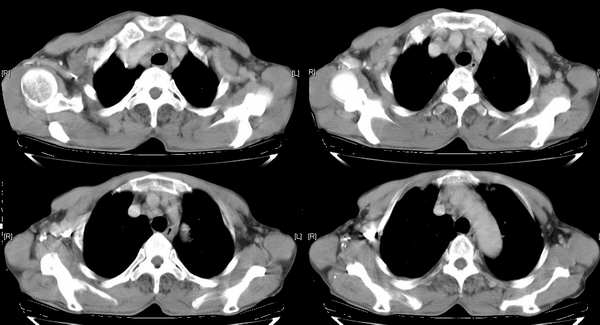

右颈部巨大软组织肿块影,范围较广,上至下颌角,下至颈静脉切迹。其最大层面位于右侧甲状腺区。肿块密度不均,其中有坏死液化区和班片状钙影,增强扫描见肿块实质区有强化。邻近结构挤压移位,部分结构侵蚀破坏,右侧多个颈深淋巴结肿大。两肺弥漫分布小结节影,以胸膜下为主,其大小不等,边缘光整。右侧胸壁亦见软组织结节影,纵隔多个淋巴结肿大及两侧锁骨上淋巴结肿大。

意见:右侧甲状腺癌并两肺、胸壁、纵隔淋巴结、颈深淋巴结、锁骨上淋巴结等广泛转移。

右侧甲状腺腺癌伴颈部纵隔淋巴结转移、纵隔淋巴结转移、肺内多发转移及胸膜转移。

右侧甲状腺癌伴两肺多发转移、纵隔淋巴结转移及胸膜转移